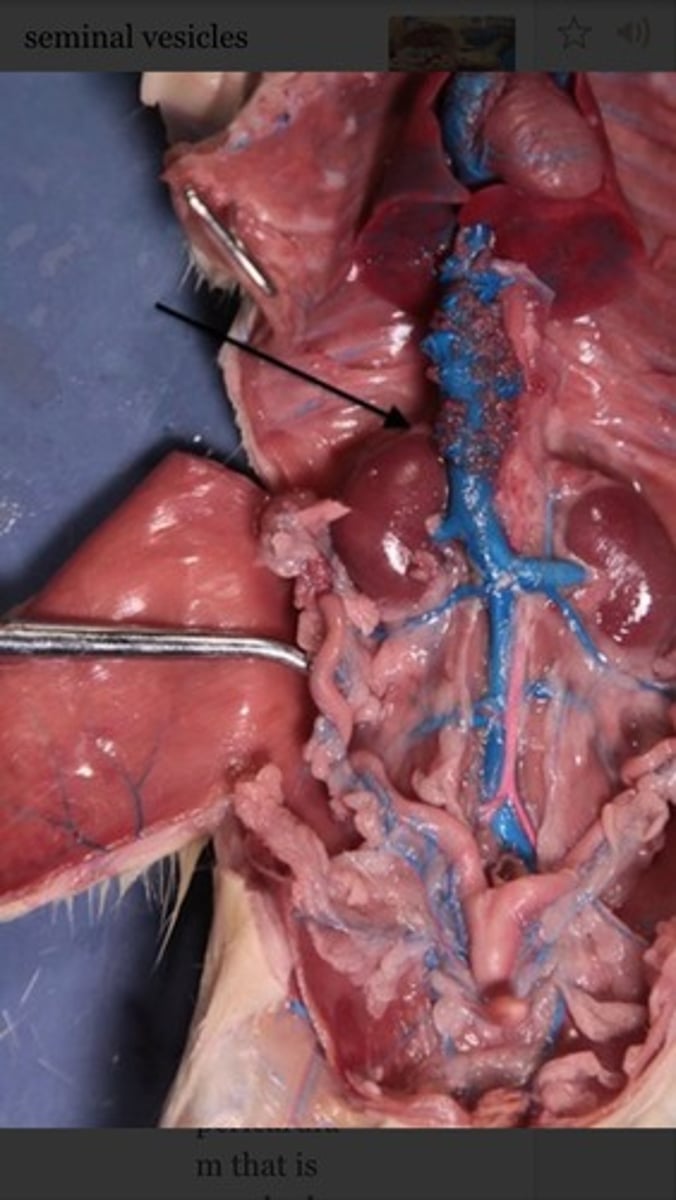

seminiferous tubules

rete testis